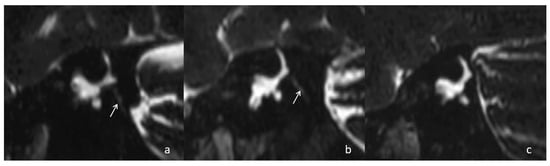

Background: Superior semicircular canal dehiscence (SSCD) is characterized by a bony defect of the superior semicircular canal (SSC), leading to vestibular and auditory symptoms. A process of spontaneous “auto-plugging,” in which the overlying dura mater progressively occludes the SSC, may replicate the effects [...] Read more.

Background: Superior semicircular canal dehiscence (SSCD) is characterized by a bony defect of the superior semicircular canal (SSC), leading to vestibular and auditory symptoms. A process of spontaneous “auto-plugging,” in which the overlying dura mater progressively occludes the SSC, may replicate the effects of surgical canal plugging but remains under-recognized. The present study reports diverse clinical, instrumental, and 3d High Resolution MRI findings in patients with SSCD and subsequently confirmed to present with spontaneous complete or partial auto-plugging. Methods: We retrospectively reviewed 11 patients with SSCD diagnosed on high-resolution CT and suspected auto-plugging based on clinical atypia and large dehiscence (>4 mm). Patients underwent comprehensive neurotological assessment, including pure-tone audiometry, vestibular testing, and HR MRI with 3D labyrinthine reconstructions to identify partial or complete auto-plugging. Auto-plugging was classified as partial (Canalis semicircularis superior depressus) or complete (absence of endolymph fluid signal; Canalis semicircularis superior obturatus). Results: Among 13 ears with auto-plugging, 6 were partial and 7 complete. The mean SSCD size in auto-plugged ears was 5.5 mm. Most ears had normal or near-normal vestibular function on VHIT, with minimal air-bone gaps and preserved VEMP responses. Imaging demonstrated varying degrees of dural contact with the SSC, confirming partial or complete canal occlusion. Conclusions: Spontaneous auto-plugging of the SSC is a plausible, under-recognized phenomenon that may reproduce functional effects of surgical plugging. Dedicated 3D labyrinthine MRI enhances detection and characterization. Prospective multimodal studies are needed to clarify the pathophysiology, progression, and clinical implications, optimizing patient selection for surgical versus conservative management. Full article